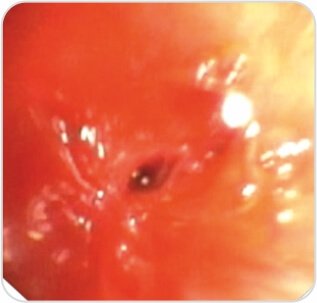

Fiber Optic Bronchoscopy revealed – Multi Level Fibrostenosis of the left main bronchus with complete obstruction of the distal LMB 2.7 cms from the primary carina and 1 cm above the second carina on the left side was noted.

Step 1